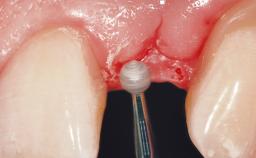

Late Placement of an Implant in a Maxillary Left Central Incisor Site

On examination, the patient had a low lip line and only displayed the coronal half of the anterior teeth when smiling.

Soft Tissue Contour and Volume | Slightly compromised |